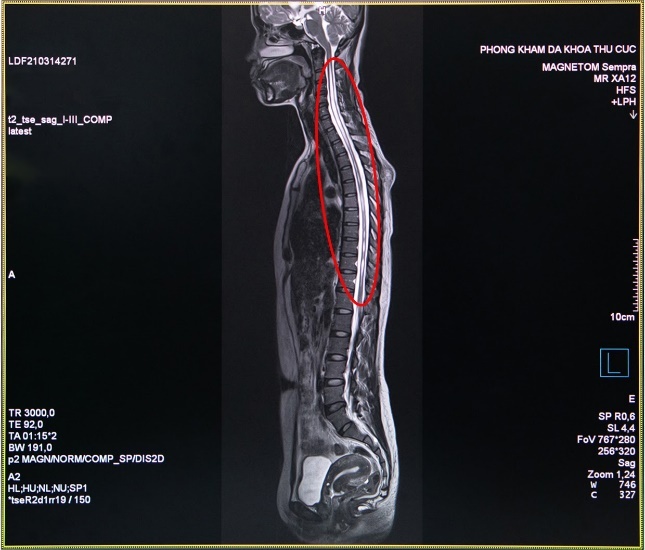

Bác sĩ chẩn đoán hình ảnh Nguyễn Chí Phồn - Phòng khám đa khoa Thu Cúc - cho biết: “Trường hợp của chị H. là chụp cộng hưởng từ MRI cột sống và tủy sống có tiêm thuốc đối quang từ, nhằm phát hiện những tổn thương thần kinh. Đây là công cụ đáng tin cậy để chẩn đoán bệnh rỗng tuỷ sống. Đối với những trường hợp nghi ngờ mắc bệnh này, nếu chỉ định chụp X- Quang hay chụp cắt lớp vi tính MSCT sẽ khó đánh giá chính xác”.

Hình ảnh thu được từ chụp cộng hưởng từ MRI tủy sống của chị H. cho thấy trong đoạn tủy sống hình thành một hốc rỗng chứa các dịch, các dịch này tích lại thành các khoang và nang hốc - biểu hiện của căn bệnh rỗng tủy. Sau khi có kết quả khám cận lâm sàng, các bác sĩ của Thu Cúc đã hội chẩn nhằm xác định căn nguyên bệnh và tìm phương pháp điều trị tốt nhất.

Hình ảnh chụp cắt lớp của người mắc bệnh tủy rỗng. |